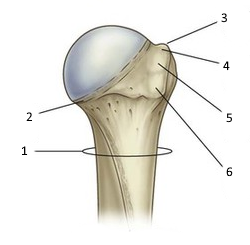

ЯК ПОЗНАЧЕНА ЧАСТИНА КІСТКИ ЩО МІСТИТЬ СТОВБУРОВІ КЛІТИНИ?

варіанти відповідей

1

2

4

3

ГУБЧАСТА РЕЧОВИНА

КІСТКОВИЙ КАНАЛ

КОМПАКТНА РЕЧОВИНА